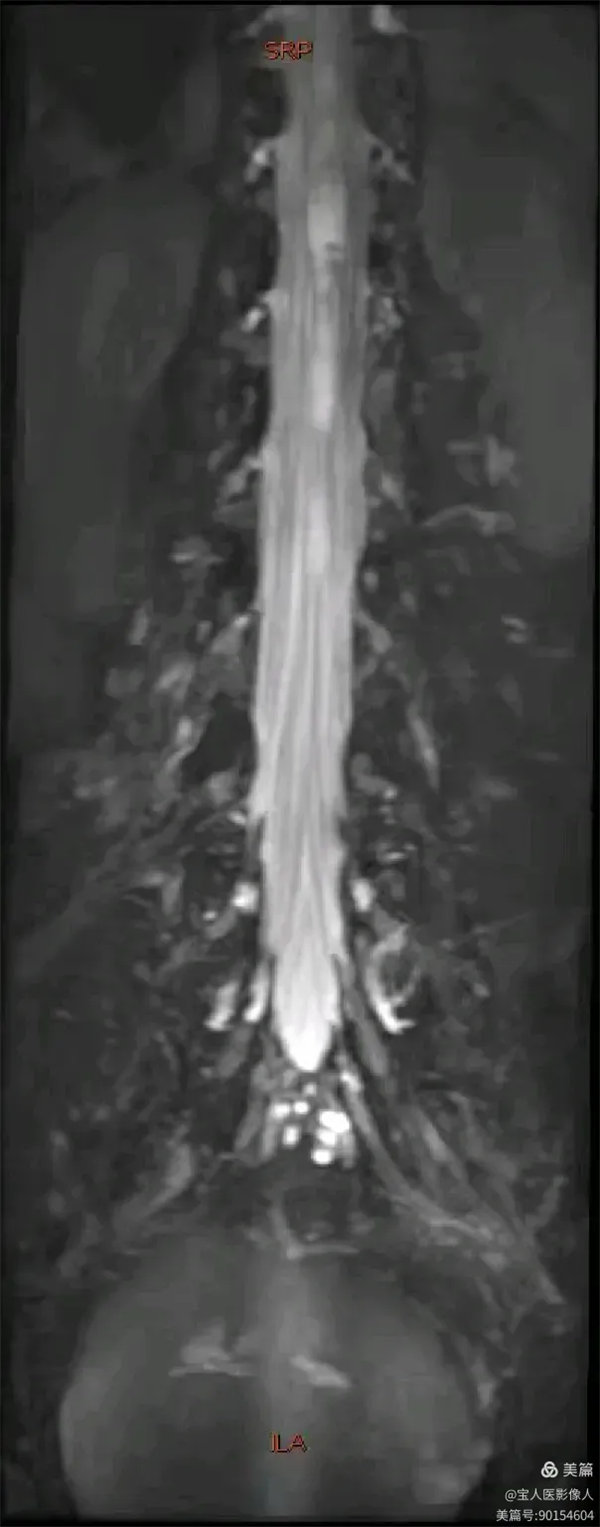

容積成像和最大密度,顯示腰段腦脊液正面圖。

最大密度正面圖,顯示腰段腦脊液(高信號),其內的馬尾神經以及腰神經(線狀稍低信號)。